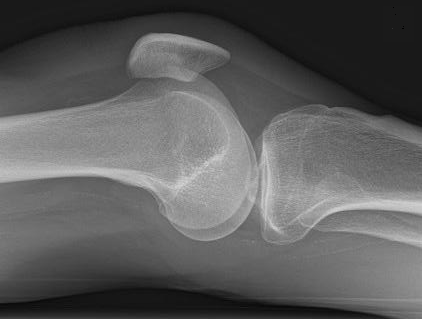

Several results from our method are shown in Fig. 7. The left column is the original input image. The right two columns are the soft tissue and bone image, respectively. It can be told that the soft tissue image is smooth as we assumed. Meanwhile, the bone image has better image contrast as desired. Moreover, our method can reach real-time performance on these X-ray images. The running time of our method on these images is reported in Table I.

Refer to caption

(a) original

(b) soft tissue

(c) bone (α=1.34𝛼1.34\alpha=1.34)

(d) original

(e) soft tissue

(f) bone (α=1.08𝛼1.08\alpha=1.08)

(g) original

(h) soft tissue

(i) bone (α=1.42𝛼1.42\alpha=1.42)

(j) original

(k) soft tissue

(l) bone (α=1.49𝛼1.49\alpha=1.49)

Figure 7: More results by our method. Input X-ray images (left), our estimated soft tissue (middle) and estimated bone image (right).